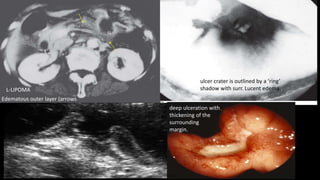

ulcer crater is outlined by a ‘ring’

shadow with surr. Lucent edema..

deep ulceration with

thickening of the

surrounding

margin.

L-LIPOMA

Edematous outer layer (arrows